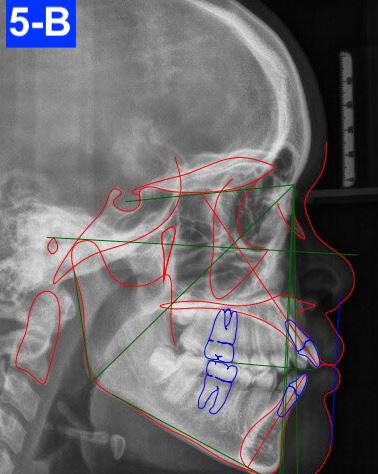

Lateral Cephalometric radiogram and tracing revealed a wide pharyngeal airway (10.0 /10.0 mm), CVMS 3-4, a prognathic maxilla (SNA - 85°), and an orthognathic mandible (SNB - 82 °). Furthermore, a Class I skeletal relationship was noted (ANB – 2.9 mm, Witts – 0.5 mm). The patient was slightly hyperdivergent (NS/GoM – 34°, ALFH – 71.8 mm), exhibited protrusive maxillary incisors (U1/SN – 118.8 ° ) with normally inclined mandibular incisors (L1/GoM 93.5°). The Harvold was 30.5 mm suggesting a Class III tendency. The soft tissue profile (lips) was convex and her Nasio-labial angle (96°) was acute (Figure 5-B).

Fig. 5-B: Pre-treatment, lateral cephalometric radiogram